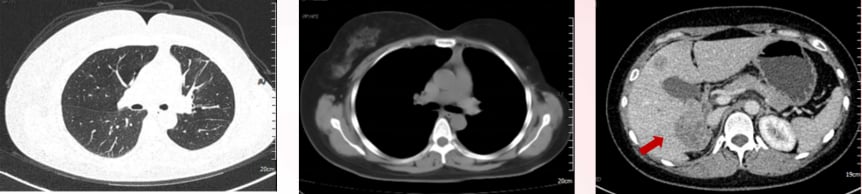

2023年11月,患者再次出现疾病进展,胸腹部CT显示肝内多发软组织肿物较前明显增多增大。肝穿刺活检病理再次确认转移性低分化腺癌,HER2(3+)阳性。

此时,患者入组了一项III期临床研究,比较FS-1502和T-DM1(恩美曲妥珠单抗)在HER2阳性不可手术切除的局部晚期或转移性乳腺癌患者中的疗效和安全性。她被随机分配到对照组,接受了14周期的恩美曲妥珠单抗治疗。恩美曲妥珠单抗是一种抗体-药物偶联物(ADC),它像一个“精准制导的化疗药”,通过抗体部分识别并结合癌细胞表面的HER2蛋白,然后将化疗药物精准地输送到癌细胞内部,减少对正常细胞的损伤。治疗后,患者肝功能异常I-II级,无骨髓抑制,疗效评价为部分缓解(PR)。临床试验不仅为患者提供了前沿治疗机会,也大大减轻了经济负担。